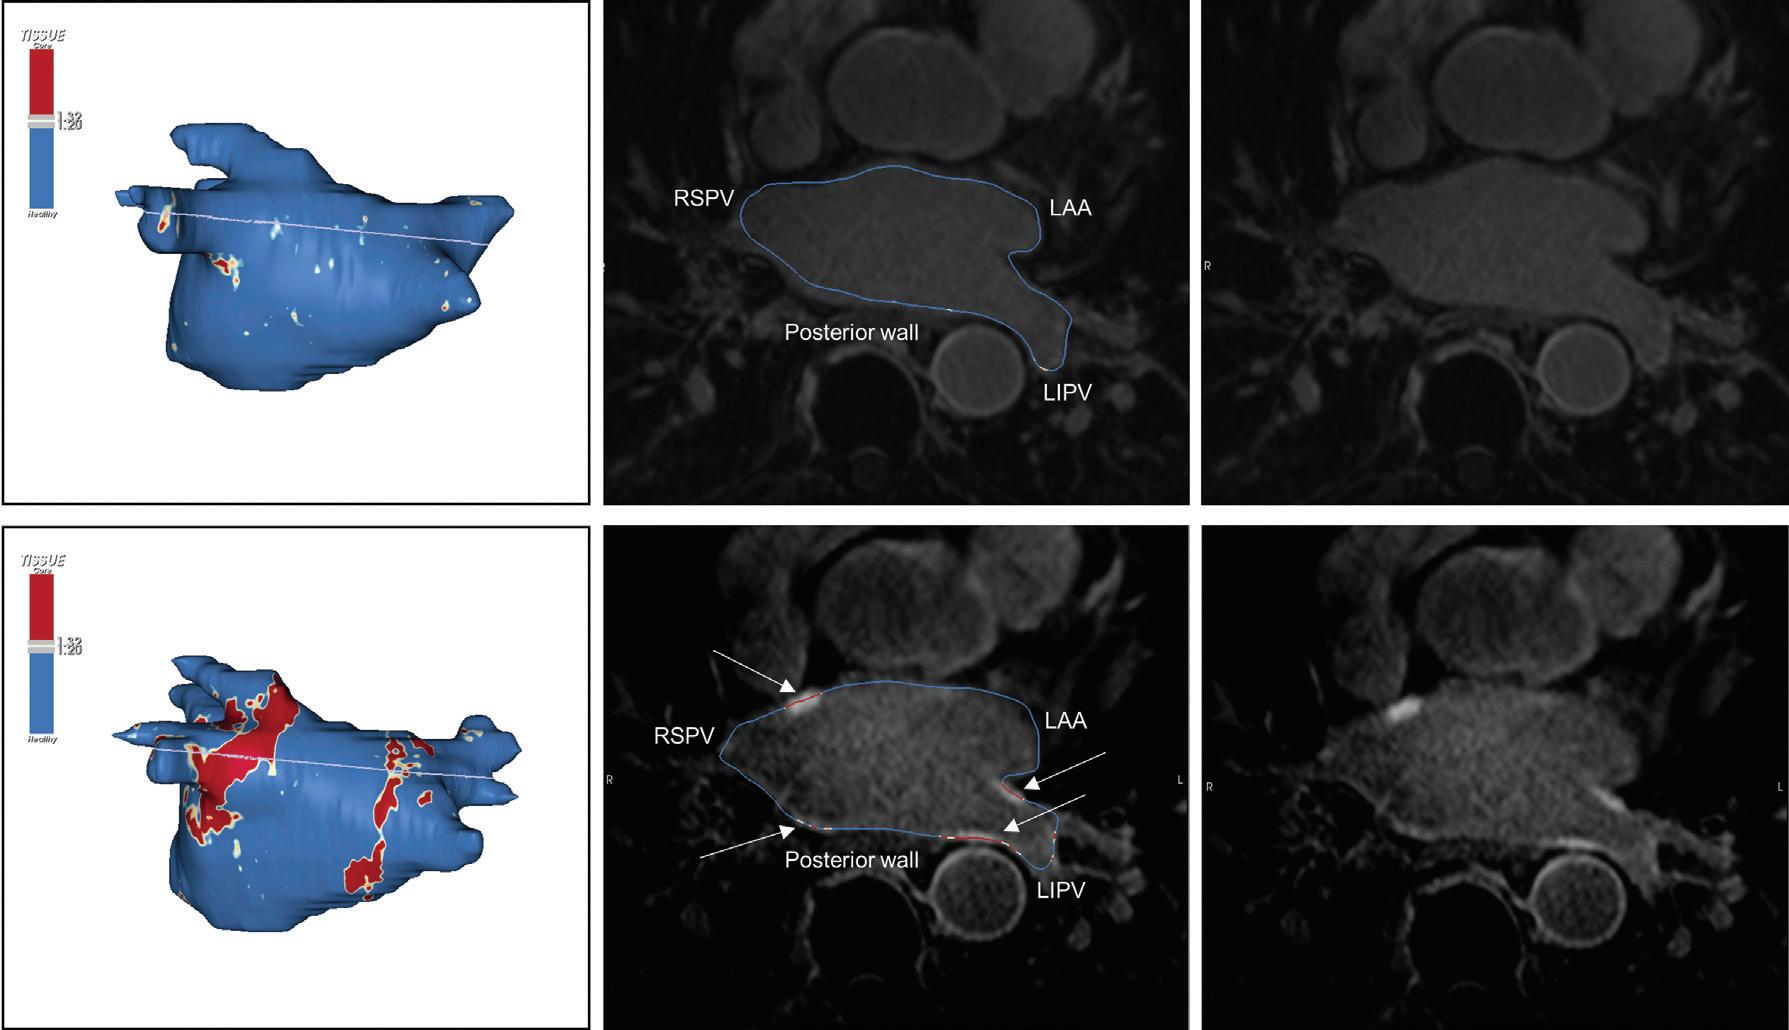

Figure 1: Ablation-induced Late Gadolinium Enhancement After Pulmonary Vein Isolation

Preprocedural LGE-MRI (1 day before PVI) Post-ablation LGE-MRI (3 months after PVI) LIPV RIPV LSPV RSPV LIPV RIPV LSPV RSPV Postero-anterior view Postero-anterior view

Left: 3D reconstruction of the LA with colour-coding based on image intensity ratios with thresholds for dense scar (red >1.32) and border zone (yellow 1.2–1.32), using ADAS 3D software (Adas3D Medical). Blue lines indicate the plane of the LA slices on the right. Middle: Overlay of the T1-weighted images with the LGE colour-coding described above. White arrows point to local ablation-induced LGE lesions. Right: T1-weighted LGE-MRI slice depicting the LA with evident LGE of PV ostial walls. LA = left atrium; LAA = left atrial appendage; LGE = late gadolinium enhancement; LIPV = left inferior pulmonary vein; LSPV = left superior pulmonary vein; PV = pulmonary vein; PVI = pulmonary vein isolation; RIPV = right inferior pulmonary vein; RSPV = right superior pulmonary vein.

Figure 2: Gaps in Ablation Lesions After Pulmonary Vein Isolation

Examples of discontinuations of ablation-induced LGE lesions encircling the right (A) and left pulmonary veins (B), respectively, in a patient with AF recurrence after PVI. Left: 3D reconstruction of the LA with colour-coding based on image intensity ratios with thresholds for dense scar (red >1.32) and border zone (yellow 1.2–1.32), using ADAS 3D software). White arrows indicate local gaps. Pink lines indicate the plane of the left atrial LGE-MRI slices on the right; Middle: Overlay of the T1-weighted left atrial slices with the LGE colour-coding described above. White arrows indicate local gaps corresponding to the ones indicated in the 3D reconstructions on the left; Right: T1-weighted LGE-MRI slices without colour-coding. LA = left atrium; LAA = left atrial appendage; LGE = late gadolinium enhancement; LIPV = left inferior pulmonary vein; LSPV = left superior pulmonary vein; PV = pulmonary vein; PVI = pulmonary vein isolation; RPV = right pulmonary vein; RIPV = right inferior pulmonary vein; RSPV = right superior pulmonary vein.